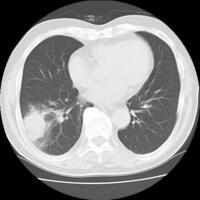

肺気腫 慢性閉塞性肺疾患 Copd 印西そよかぜ内科 呼吸器内科